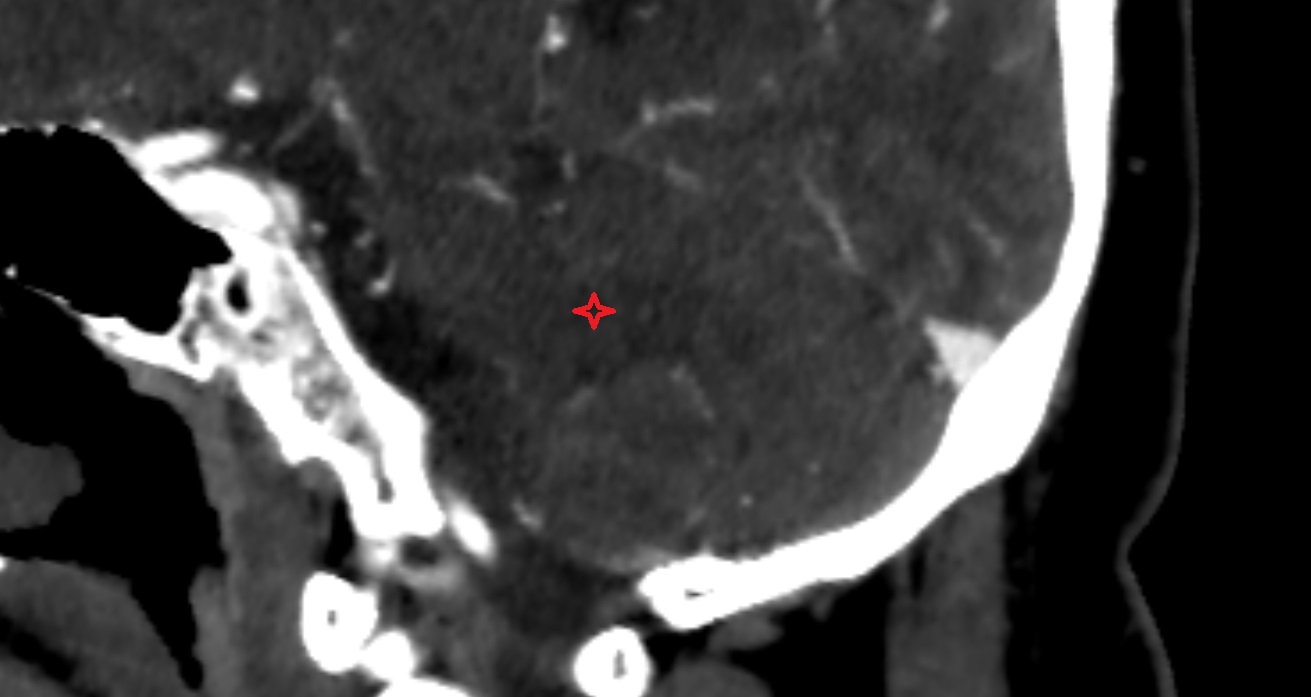

- Liver Segment I – Caudate lobe

- Liver Segment II – Left lateral superior segment

- Liver Segment III – Left lateral inferior segment

- Liver Segment IVa – Left medial superior segment

- Liver Segment IVb – Left medial inferior segment

- Liver Segment V – Right anteroinferior segment

- Liver Segment VI – Right posteroinferior segment

- Liver Segment VII – Right posterosuperior segment

- Liver Segment VIII – Right anterosuperior segment